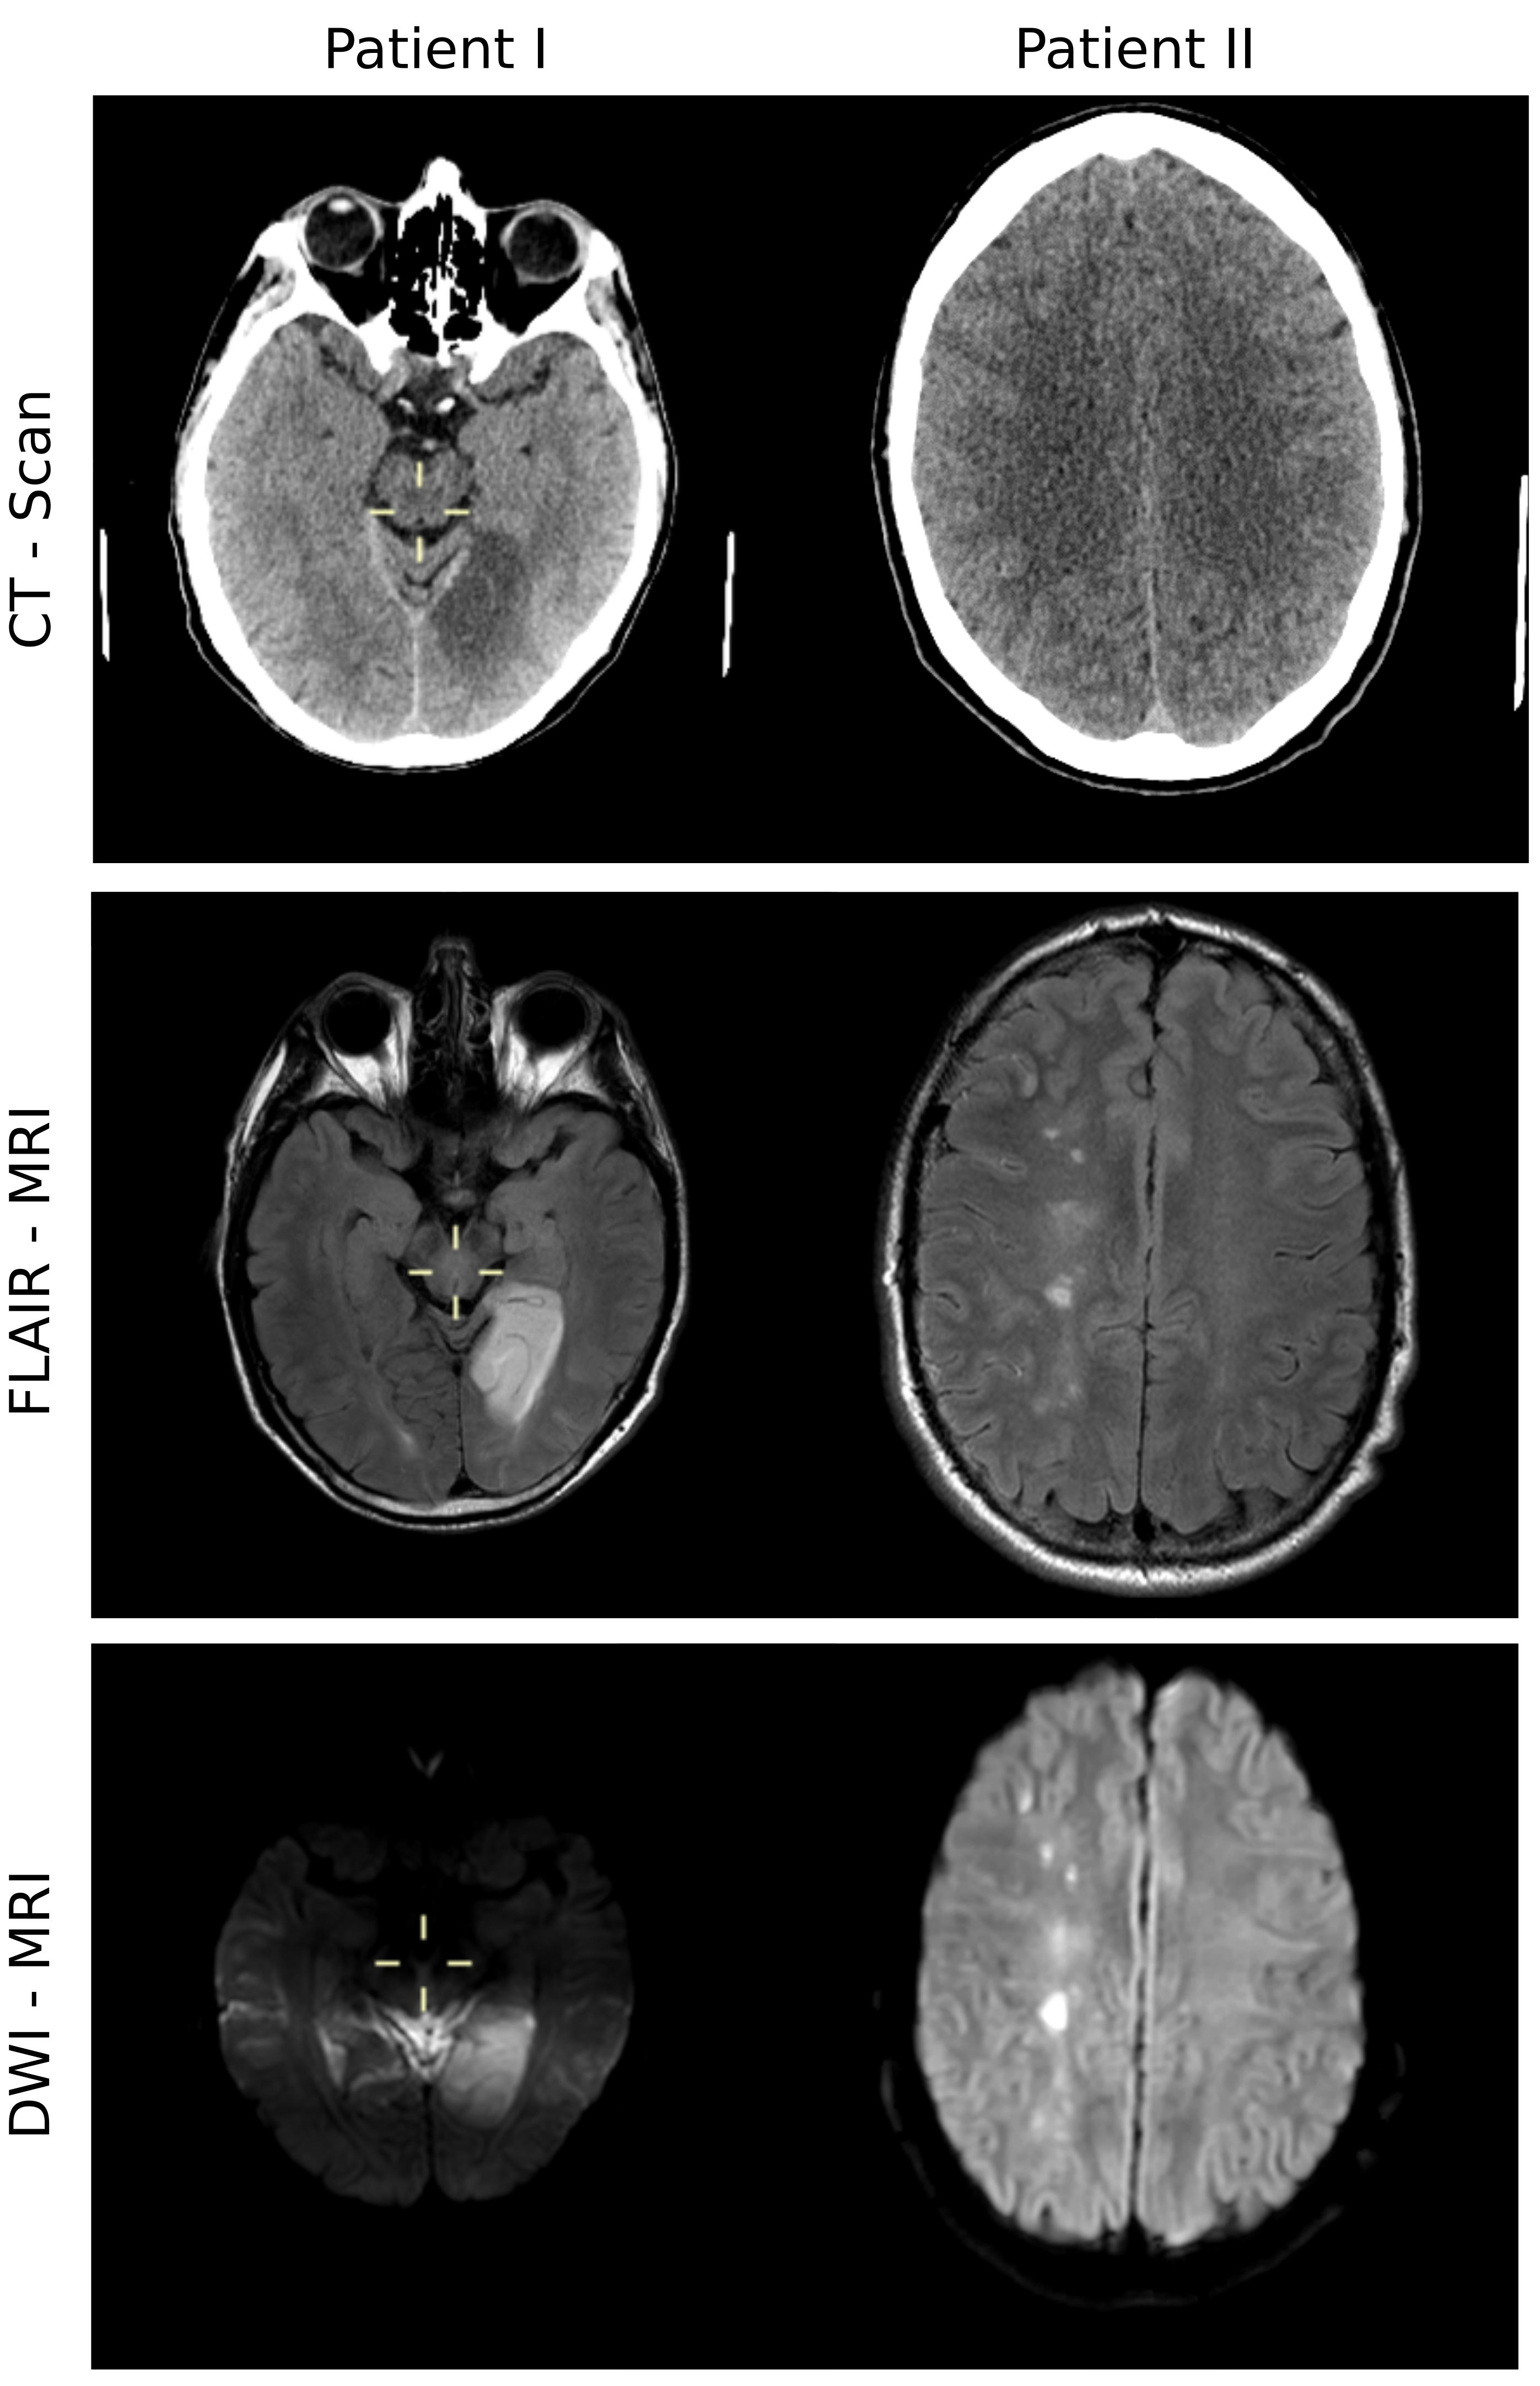

3.2 In vivo FFC imaging data

The performance of the proposed method was tested on in vivo FFC imaging patient data. Two data sets obtained from patients scanned for a brain stroke were selected, as part of the PUFFINS study currently taking place at the University of Aberdeen. This study has been approved by the North of Scotland Research Ethics Committee (study number 16/NS/0136) and all the participants agreed for the clinical and FFC imaging data to be used anonymously for research purposes. The scans selected both present a lesion in the ultra-low field regime that could not be easily observed at 200 mT, as illustrated in Figure 2 for patient I. Both cases were assessed from computed tomography (CT) and diffusion-weighted MRI scans as embolic stroke for patient I and multiple embolic events for patient II. FFC measurements were performed using a whole-body FFC scanner [21] using a FFC inversion-recovery spin echo sequence [46] with an echo time of 24 ms, 20 kHz bandwidth, 8.37 MHz acquisition frequency, 10 mm slide thickness and single slice acquisition. The images had a field of view of 290 mm and a resolution of 128 x 128 pixel in-plane with 80 phase encode acquisitions and partial Fourier acquisition (80 lines out of 128). The sample was pre-polarised at 200 mT for 300 ms before each evolution periods with the timings as shown in Table  1, for an acquisition time of 40 min.

The improvements in T1subscript𝑇1T_{1} estimations held true when processing real FFC imaging data from stroke patients. The T1subscript𝑇1T_{1} maps of unfiltered FFC images obtained using standard fitting-based processing methods could not resolve anatomical features inside the brain region, as seen in Figures 6 and 7. Spatial regularization in combination with multi-field fitting could greatly improve image contrast. The proposed method offers clear distinguishable structures in T1subscript𝑇1T_{1} maps at 200 mT and is even able to recover some structural details in lower fields. It also assessed sharp features around the lesion area appearing at 37 mT and below in both patients. Fitting took approximately 65 and 150 seconds with the standard method for patient I and II, respectively, whereas the proposed method took 100 and 240 seconds for each patient, respectively.

The advantages of the improved fitting approach become immanent in the in vivo applications (Figures 6 and 7). The standard approaches based on pixel-wise fitting fail to reconstruct image details in both patients. In current practice, k-space windowing filters are applied to recover usable information but this dramatically reduces image resolution by filtering out the high-frequency components of the image, which are responsible for the sharp features. In contrast, the joint regularization approach can recover clearly distinguishable grey and white matter regions at 200 mT on the two patient datasets, previously hidden in noise. The values obtained for the different regions of interest agree well between the patients, given the estimation of the error provided by the variation of the T1subscript𝑇1T_{1} values within each ROI (Figure 8). The T1subscript𝑇1T_{1} values were systematically higher in patient I than in patient II, which may be attributed to patient variability and different RF receive coil sensitivity relative to the used ROIs. In addition, lesion localization agrees well with conventional MRI and CT based imaging, shown in Supporting Information Figure 1.

Figure 6: In vivo multi-field T1subscript𝑇1T_{1} maps of a transverse slice of the brain of stroke patient I. From top to bottom, T1subscript𝑇1T_{1} maps were obtained at three different evolution fields B0E={200,21.1,2.2}mTsuperscriptsubscript𝐵0𝐸20021.12.2𝑚𝑇B_{0}^{E}=\{200,~{}21.1,~{}2.2\}~{}mT by pixel-wise fitting of the signal model for each B0Esuperscriptsubscript𝐵0𝐸B_{0}^{E} separately, combined field pixel-wise fitting, multi-field model-based reconstruction with H1 regularization and by the proposed multi-field model-based reconstruction approach utilizing the joint information of all three evolution fields (bottom row).

Figure 7: In vivo multi-field T1subscript𝑇1T_{1} maps of a transverse slice of the brain of stroke patient II. T1subscript𝑇1T_{1} maps were obtained at four different evolution fields B0E={200,37,6.9,1.3}superscriptsubscript𝐵0𝐸200376.91.3B_{0}^{E}=\{200,~{}37,~{}6.9,~{}1.3\} mT. The different reconstruction methods are given in each row. From top to bottom the methods are pixel-wise fitting of the signal model for each B0Esuperscriptsubscript𝐵0𝐸B_{0}^{E} separately, combined field pixel-wise fitting, multi-field model-based reconstruction with H1 regularization and by the proposed multi-field model-based reconstruction approach utilizing the joint information of all three evolution fields.